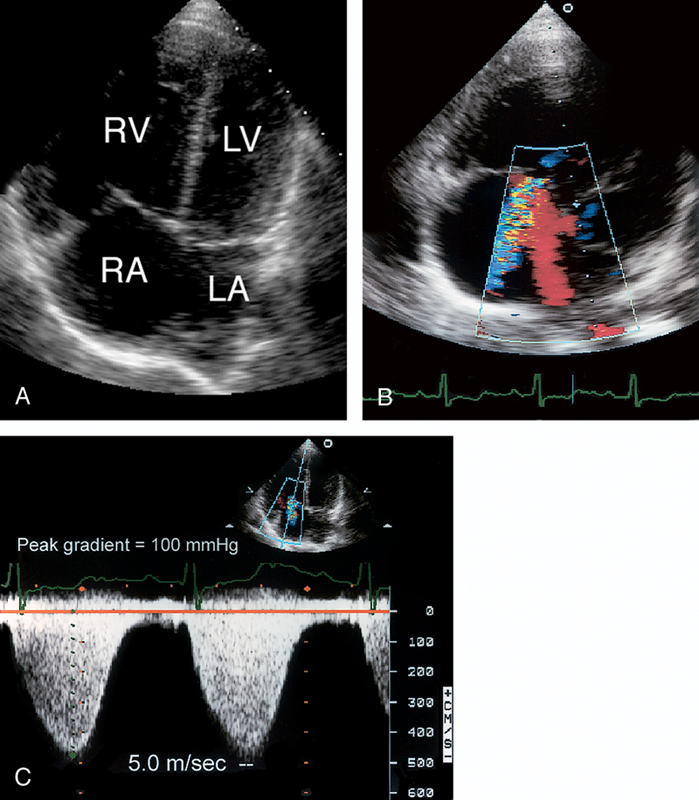

فحوصات تشخيصية لبعض امراض القلب والشرايين التاجية